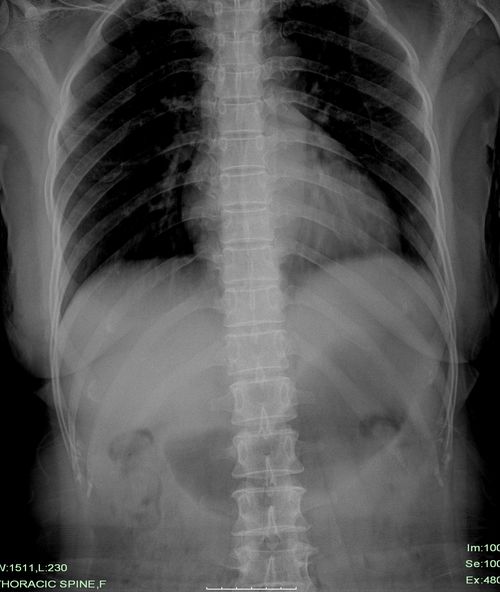

标题: X6328:M45,l阑尾炎术后5天,胸背痛渐进加重。 [打印本页]

标题: X6328:M45,l阑尾炎术后5天,胸背痛渐进加重。

膈下未见游离气体。

男性还是女性?要是男性乳房影也忒发达了!胸片双肺未见明显异常,侧位片示主动脉管径增宽;kub未包括盆腔,片内未见明显气液平面及膈下游离气体。

胃扩张

胃扩张.支持!

胃扩张.支持

考虑胃扩张。术后胃肠功能较差造成的